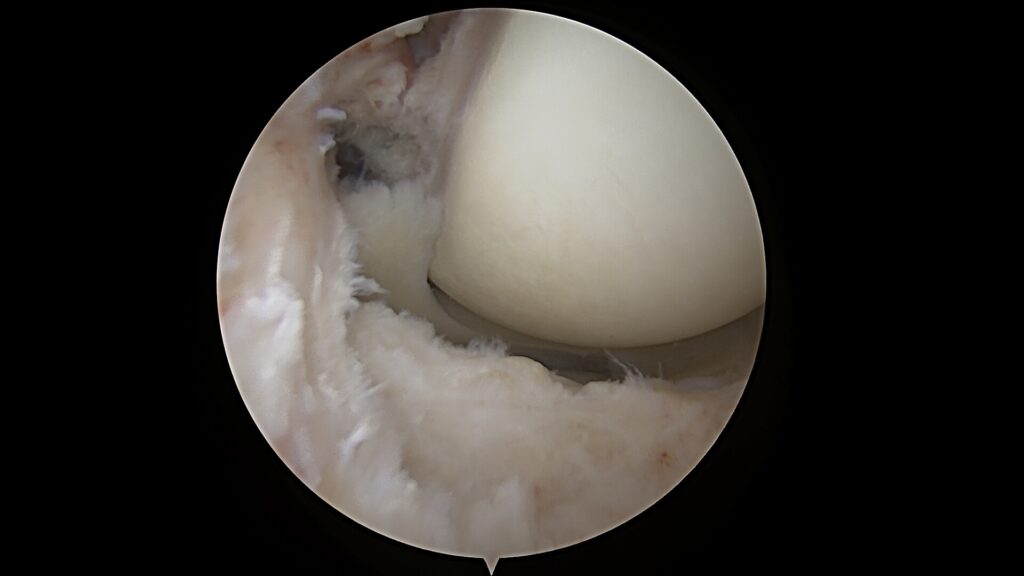

2. Išorinio menisko šaknies fiksacija su DRILLBONE sistema

Šaknies fiksacija leidžia atkurti menisko apkrovos perdavimo gebėjimą – tai esminis žingsnis siekiant fiziologiškos kelio biomechanikos.